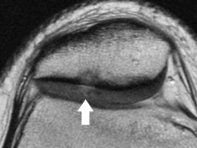

The philosophy is not to turn a noninvasive study into an invasive study. We use hardly any intra-articular contrast, but have changed the pulse sequence to the extent that we can visualize cartilage, which we see as one of the prime early determinants of arthritis, both osteoarthritis and inflammatory arthritis. This is something you want to visualize with exquisite detail.

We are doing T2 mapping and are doing special studies to try to evaluate cartilage changes at the microscopic level, at the occult level, before someone putting in an arthroscope would see it.

![]() ![]() |

| Axial cartilage-sensitive fast-spin echo MR image (left) of the patellofemoral joint of the knee in an 18-year-old patient demonstrates focal signal hyperintensity of the articular cartilage (arrow) identified centrally in the lateral facet, with delamination from the deep components, starting at the radial zone adjacent to the tidemark. Note the associated deformity of the subchondral bone with sclerosis. Corresponding quantitative T2 relaxation time color map (right) coded to capture T2 values ranging from 10 to 90 msec, with green and blue reflecting longer T2 values, yellow intermediate, and orange the shorter values, demonstrates striking prolongation of T2 values over the basilar component at this site, which is an indication of breakdown in the collagen component of the extracellular matrix. Note that the thickness of the cartilage is unaffected. Images courtesy of the Hospital for Special Surgery. |